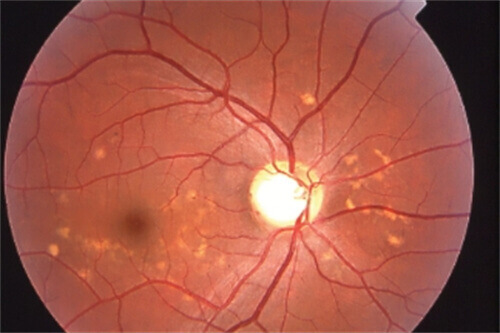

45岁糖尿病患者王先生,因视力骤降就诊,确诊为增殖性糖尿病视网膜病变伴玻璃体出血。

孙医生为其多期实施玻璃体切割手术联合全视网膜光凝,术后6个月视力从0.1修复至0.6。

类似实例中,80%患者术后视力得到显著改善,并发症发生率低于5%。

临床数据显示,孙医生主刀的视网膜复位手术成功几率达92.3%,其中:

原发性视网膜脱离患者术后视力改善率85%

糖尿病黄斑水肿患者视力稳定率91%

高度近视黄斑裂孔闭合率89%